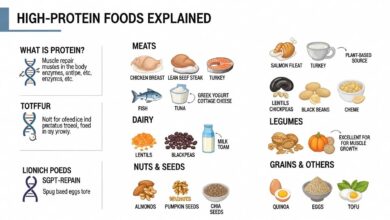

यह देखा गया है कि ओमेगा-3 फैटी एसिड से Joint pain के स्वास्थ्य के लिए कई लाभ होते हैं। ये आवश्यक वसा अपने सूजनरोधी गुणों के लिए जाने जाते हैं, जो गठिया जैसी स्थितियों से प्रभावित जोड़ों में दर्द और सूजन को कम करने में मदद कर सकते हैं। ओमेगा-3 उपास्थि की संरचनात्मक अखंडता को बनाए रखने में भी महत्वपूर्ण भूमिका निभाता है, संयोजी ऊतक जो हमारे जोड़ों को सहारा देता है और उन्हें सुचारू रूप से चलने में मदद करता है।

अपने आहार में ओमेगा-3 फैटी एसिड के स्रोतों, जैसे मछली के तेल की खुराक या सैल्मन, अखरोट और अलसी जैसे खाद्य पदार्थों को शामिल करने से आपके जोड़ों को पोषण देने और समग्र संयुक्त स्वास्थ्य को बढ़ावा देने में मदद मिल सकती है। इसके अतिरिक्त, शोध से पता चलता है कि ओमेगा-3 संयुक्त समस्याओं वाले व्यक्तियों में बेहतर गतिशीलता और लचीलेपन में भी योगदान दे सकता है। कुल मिलाकर, स्वस्थ जोड़ों का समर्थन करने और दीर्घकालिक संयुक्त क्षति को रोकने के लिए ओमेगा -3 सेवन को प्राथमिकता देना एक स्मार्ट विकल्प है।